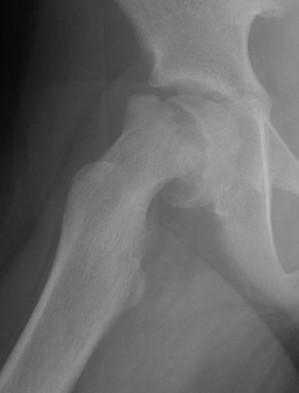

Deformity

Varus / extension / external rotation

Osteotomy

Valgus / flexion / internal rotation